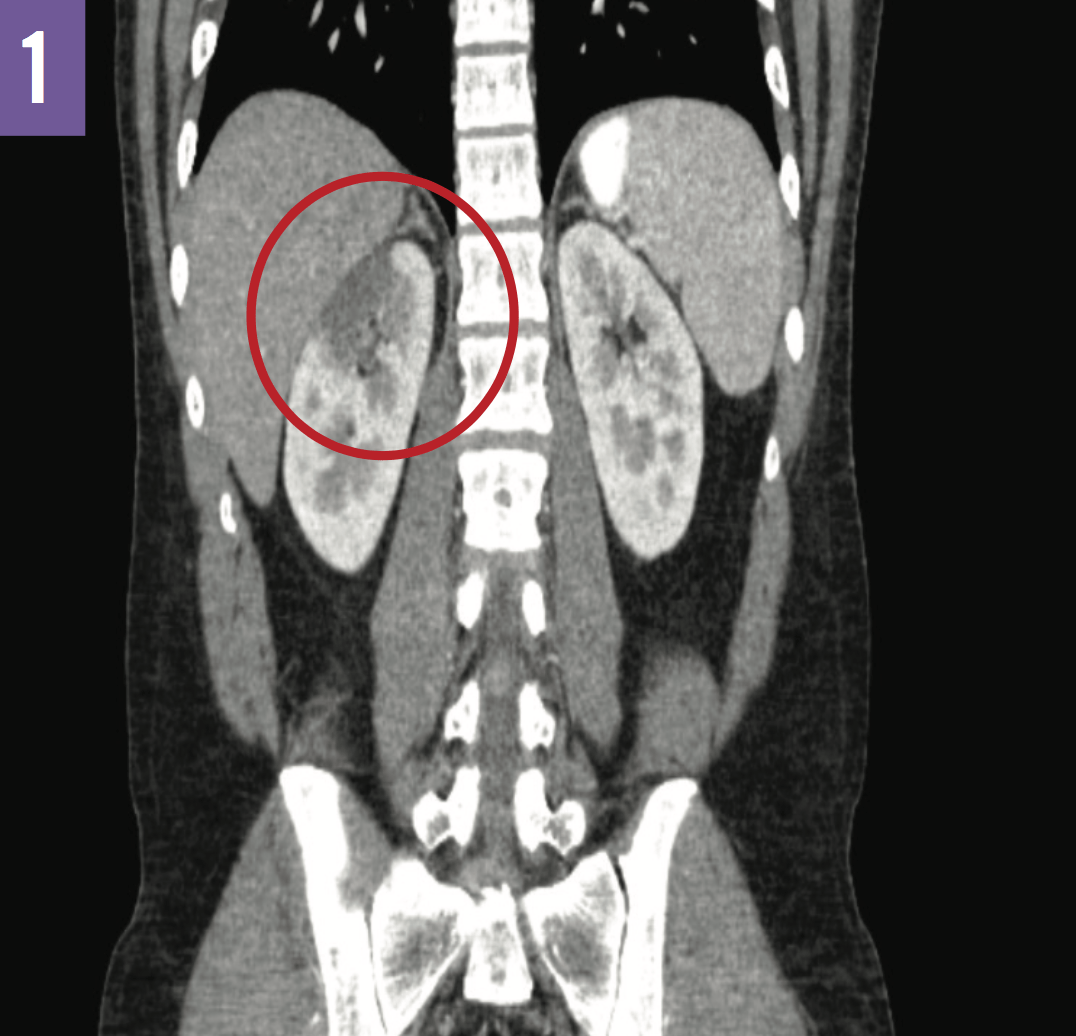

Renal Infarction in EhlersDanlos Syndrome Consultant360 Ehlers-Danlos And Kidney Problems Eds is characterized by hypermobile joints and a deficiency in collagen (connective tissue) that results. Whenever the blood circulation to the kidneys is stopped, it is referred to as a renal infarction (or kidney failure). Srad is an emerging cause of kidney infarction that accounts for a relevant portion, if not the majority, of the cases occurring in the absence. Ehlers-Danlos And Kidney Problems.